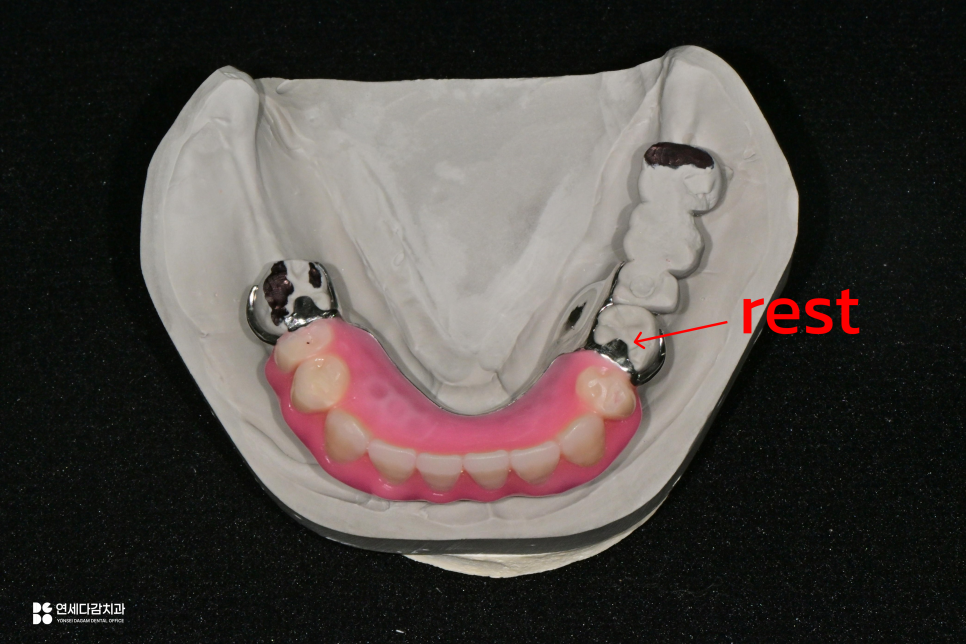

또한 서베이드 크라운과 함께

안정성의 핵심이 되는 것이

레스트 시트(rest seat)입니다.

지대치 교합면에 만드는 오목한 홈으로,

부분틀니의 레스트가 안착하는 자리입니다.

이 구조가 있어야 교합력이 분산될 수 있고,

틀니가 위아래로 들뜨거나 불필요한

움직임을 막을 수 있습니다.

이 레스트 시트의 위치와 형태는

설계에 따라서 달라질 수 있습니다.

예를 들어 인접면 교합 레스트 시트

(interproximal occlusal rest seat)는

두 치아 사이 접촉부위에 홈을 만들어 주어

유지력을 보다 높게 형성할 수 있습니다.

다만 이 경우 두 치아의 보철을

새로 제작해야 합니다.

왼쪽 아래의 경우 Interproximal rest seat를 해드리는 것이

제일 좋아보였으나, 이렇게 진행을 하기 위해선

왼쪽 아래 임플란트 보철물을 모두 제거하고

새로 만들어야 하는 상황이 었습니다.

환자분께서는 왼쪽 아래 보철물을 전부 교체하는 과정을

부담스러워 하셔서 유지력을 조금 더 포기하더라도

치아 하나에만 rest seat를 제작하게 되었습니다.